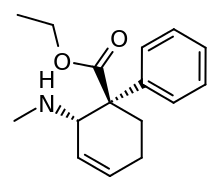

The pharmacodynamic response to an opioid depends upon the receptor to which it binds, its affinity for that receptor, and whether the opioid is an agonist or an antagonist. For example, the supraspinal analgesic properties of the opioid agonist morphine are mediated by activation of the μ1 receptor; respiratory depression and physical dependence by the μ2 receptor; and sedation and spinal analgesia by the κ receptor. Each group of opioid receptors elicits a distinct set of neurological responses, with the receptor subtypes (such as μ1 and μ2 for example) providing even more [measurably] specific responses. Unique to each opioid is its distinct binding affinity to the various classes of opioid receptors (e.g. the μ, κ, and δ opioid receptors are activated at different magnitudes according to the specific receptor binding affinities of the opioid). For example, the opiate alkaloid morphine exhibits high-affinity binding to the μ-opioid receptor, while ketazocine exhibits high affinity to ĸ receptors. It is this combinatorial mechanism that allows for such a wide class of opioids and molecular designs to exist, each with its own unique effect profile. Their individual molecular structure is also responsible for their different duration of action, whereby metabolic breakdown (such as N-dealkylation) is responsible for opioid metabolism.

Several semi-synthetic opioids were developed in Germany in the 1910s. The first, oxymorphone, was synthesized from thebaine, an opioid alkaloid in opium poppies, in 1914.[228] Next, Martin Freund and Edmund Speyer developed oxycodone, also from thebaine, at the University of Frankfurt in 1916.[229] In 1920, hydrocodone was prepared by Carl Mannich and Helene Löwenheim, deriving it from codeine. In 1924, hydromorphone was synthesized by adding hydrogen to morphine. Etorphine was synthesized in 1960, from the oripavine in opium poppy straw. Buprenorphine was discovered in 1972.[228]

The first fully synthetic opioid was meperidine (later demerol), found serendipitously by German chemist Otto Eisleb (or Eislib) at IG Farben in 1932.[228] Meperidine was the first opiate to have a structure unrelated to morphine, but with opiate-like properties.[199] Its analgesic effects were discovered by Otto Schaumann in 1939.[228] Gustav Ehrhart and Max Bockmühl, also at IG Farben, built on the work of Eisleb and Schaumann. They developed "Hoechst 10820" (later methadone) around 1937.[230] In 1959 the Belgian physician Paul Janssen developed fentanyl, a synthetic drug with 30 to 50 times the potency of heroin.[211][231] Nearly 150 synthetic opioids are now known.[228]